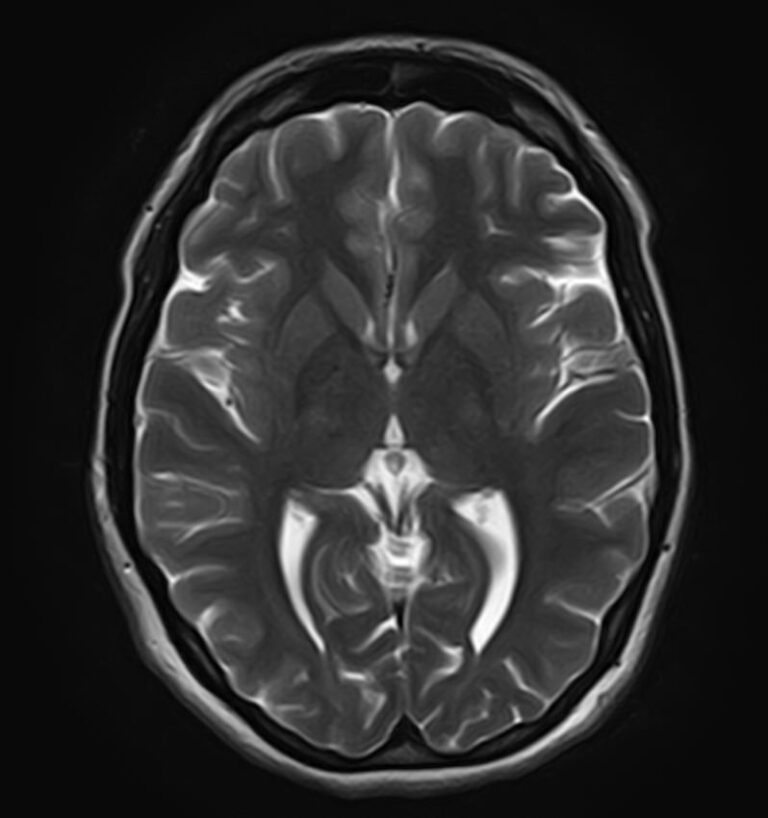

К центральной нервной системе организма относится головной мозг, расположенный в полости черепа, и спинной мозг, проходящий в спинномозговом канале позвоночного столба. В головном мозге находятся высшие центры управления всем организмом, спинной мозг имеет двусторонние связи с ними, то есть является проводником импульсов от периферии к головном мозгу и обратно.

Для диагностики заболеваний ЦНС в клинике «Доступная медицина» проводится комплексное обследование МРТ ЦНС (центральной нервной системы). Клиника укомплектована высокотехнологичным оборудованием, в частности, новейшим 32-канальным высокопольным томографом TOSHIBA VANTAGE TITAN 1,5 Тесла с высокой разрешающей способностью для точной диагностики заболеваний центральной нервной системы.

Комплексное обследование ЦНС выполняется как в стандартном режиме, когда не применяется использование контраста, так и с контрастным усилением. Для более точной диагностики некоторых патологий головного и спинного мозга внутривенно вводится контрастное вещество. С помощью контраста можно обнаружить опухолевые образования размером от 1 мм, демиелинизирующие процессы, дегенеративно-дистрофические заболевания, воспалительные процессы, сосудистую патологию.